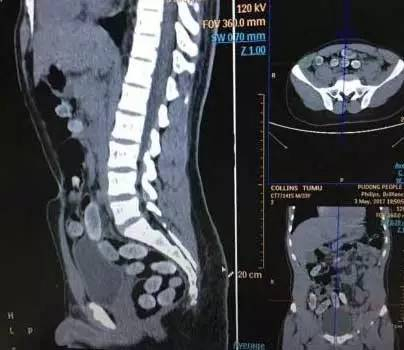

说到卫生,顺便提一下那些人体藏毒的案例,小包毒品都是吞服后经过食道、胃、肠道……它的路径可以说和大便完全一致。所以,某些人吸的毒,来路可以说是非常恶心了。